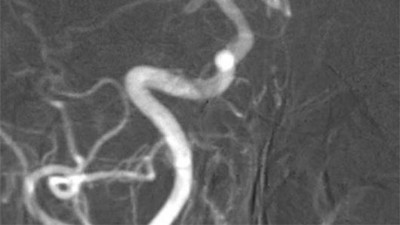

„K nehodě došlo 17. srpna mezi obcemi Patokryje a Lužice. Řidič osobního vozu předjížděl čtyři další auta. Náš kamarád Mára v tu chvíli jel na motorce a tento řidič jej srazil. Mára skončil s otevřenou zlomeninou, zdravotníci se snažili na poli najít kus kolene, aby mu tu nohu mohli dát dohromady. Po pár týdnech ale bylo jasné, že mu nohu musí vzít," popsala stručně tragický příběh Martina Vítková.

Marek stále neměl vyhráno, po amputaci jej čekala další operace ruky a druhé nohy. „Domů jej pustili 17. září, tedy měsíc po nehodě. Teď se učí být samostatný, rehabilituje. To vše stojí mnoho peněz, byli bychom šťastní, kdyby mohl získat kvalitní protézu, aby se mohl zase postavit na obě nohy," uzavírá Martina Vítková.